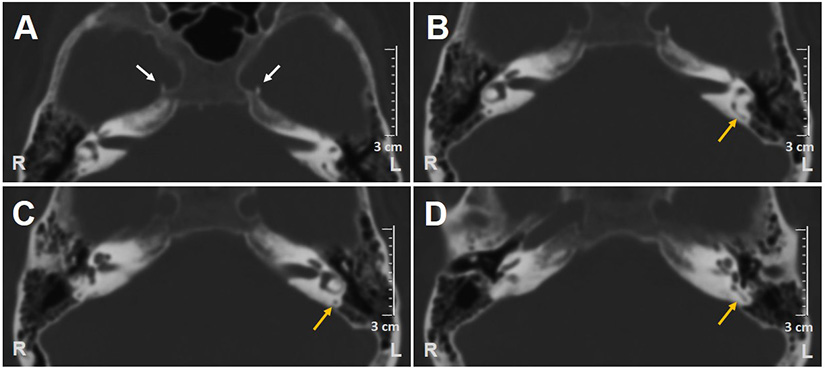

A 62-year-old male with acute vertigo, unsteadiness, nausea, and vomiting was admitted to the emergency department. He denied recurrent headaches and significant auditory symptoms. His clinical history was consistent with hypercholesterolemia and acid reflux. Six years earlier, he had presented with a sudden flat right-sided sensorineural HL that recovered fully on oral steroids. On admission, neurological evaluation and bedside oculomotor testing (including saccades, smooth pursuit, and test of skew) excluded signs of central nervous system (CNS) involvement. Both blood pressure and pulse rate were within normality ranges, and electrocardiography was unremarkable. Only slight signs of bilateral carotid siphon calcifications were noted on a standard brain CT scan (Figure 1A), whereas serology for SARS-CoV-2 was negative. Otoneurological examination with monocular video-Frenzel goggles detected spontaneous vertical DBN inhibited by visual fixation while slightly enhanced by 100 Hz-mastoid vibrations and head shaking. In addition, horizontal right beating components could be detected in a supine position, whereas neither bilateral gaze nor hyperventilation tests changed spontaneous oculomotor patterns (Supplementary Video 1). No corrective saccades could be detected on the horizontal bedside HIT, and moderate-to-severe ataxia was found in the Romberg test. Therefore, the patient was scheduled for an additional CT scan 48 hours later to rule out a posterior fossa stroke. New imaging still excluded abnormal findings in the brainstem and the cerebellum. Despite low-resolution scans and thick slices, normal patency and morphology of the inner ear structures could be verified in temporal bone scans (Figures 1B–D). The patient was then submitted to an extensive instrumental assessment. On micro-otoscopy, tympanic membranes were unremarkable, impedance audiometry was normal, while pure tone audiometry detected bilateral sensorineural high-frequency HL, with noise-induced components slightly greater in the right ear, comparable to the previous audiogram (Figure 2A). Video-HIT documented a severe impairment for the left PSC VOR-gain (0.37) with mainly overt saccades (Figure 2B), whereas bithermal caloric irrigations were within normality ranges. While O-VEMPs were symmetrical, C-VEMPs revealed no responses on the left side, consistent with saccular impairment (Figure 2C). A gadolinium-enhanced brain MRI performed the following week only showed signs of periventricular leukoaraiosis, with normal findings in the posterior fossa. Therefore, left-sided IVN was diagnosed according to clinical and instrumental findings. Despite a first therapeutic approach including steroids, vestibular suppressants, and antiemetic drugs followed by a 3-month pharmacological treatment enhancing vestibular compensation (Betahistine 24 mg twice a day and Citicoline 1 g a day), the patient kept complaining of continuous unsteadiness and oscillopsia, particularly walking down the stairs. He was then sent to a tertiary referral center for vestibular dysfunction. The persistence of slight spontaneous DBN inhibited by visual fixation was ascertained on video-Frenzel examination. Skull vibration greatly enhanced spontaneous nystagmus and a new video-HIT confirmed the left PSC hypoactivity, despite a slight VOR-gain improvement (0.54) (Figure 3A). A cone-beam CT scan of the temporal bones was scheduled to exclude possible semicircular canal dehiscences. Surprisingly, a sub-total left PSC ossification was found (Figure 3B), consistent with ischemic damage in the labyrinthine territory supplied by the PVA. Prophylactic treatment with acetylsalicylic acid was then suggested, and the patient was advised to undergo vestibular rehabilitation therapy. Written informed consent was obtained from the patient to publish this case report, including all data and images.

Figure 1

Axial scans of brain CT show (A) bilateral carotid siphon calcifications (white arrows) and (B–D) patent left PSC (yellow arrows). CT, computed tomography; L, left; PSC, posterior semicircular canal; R, right.